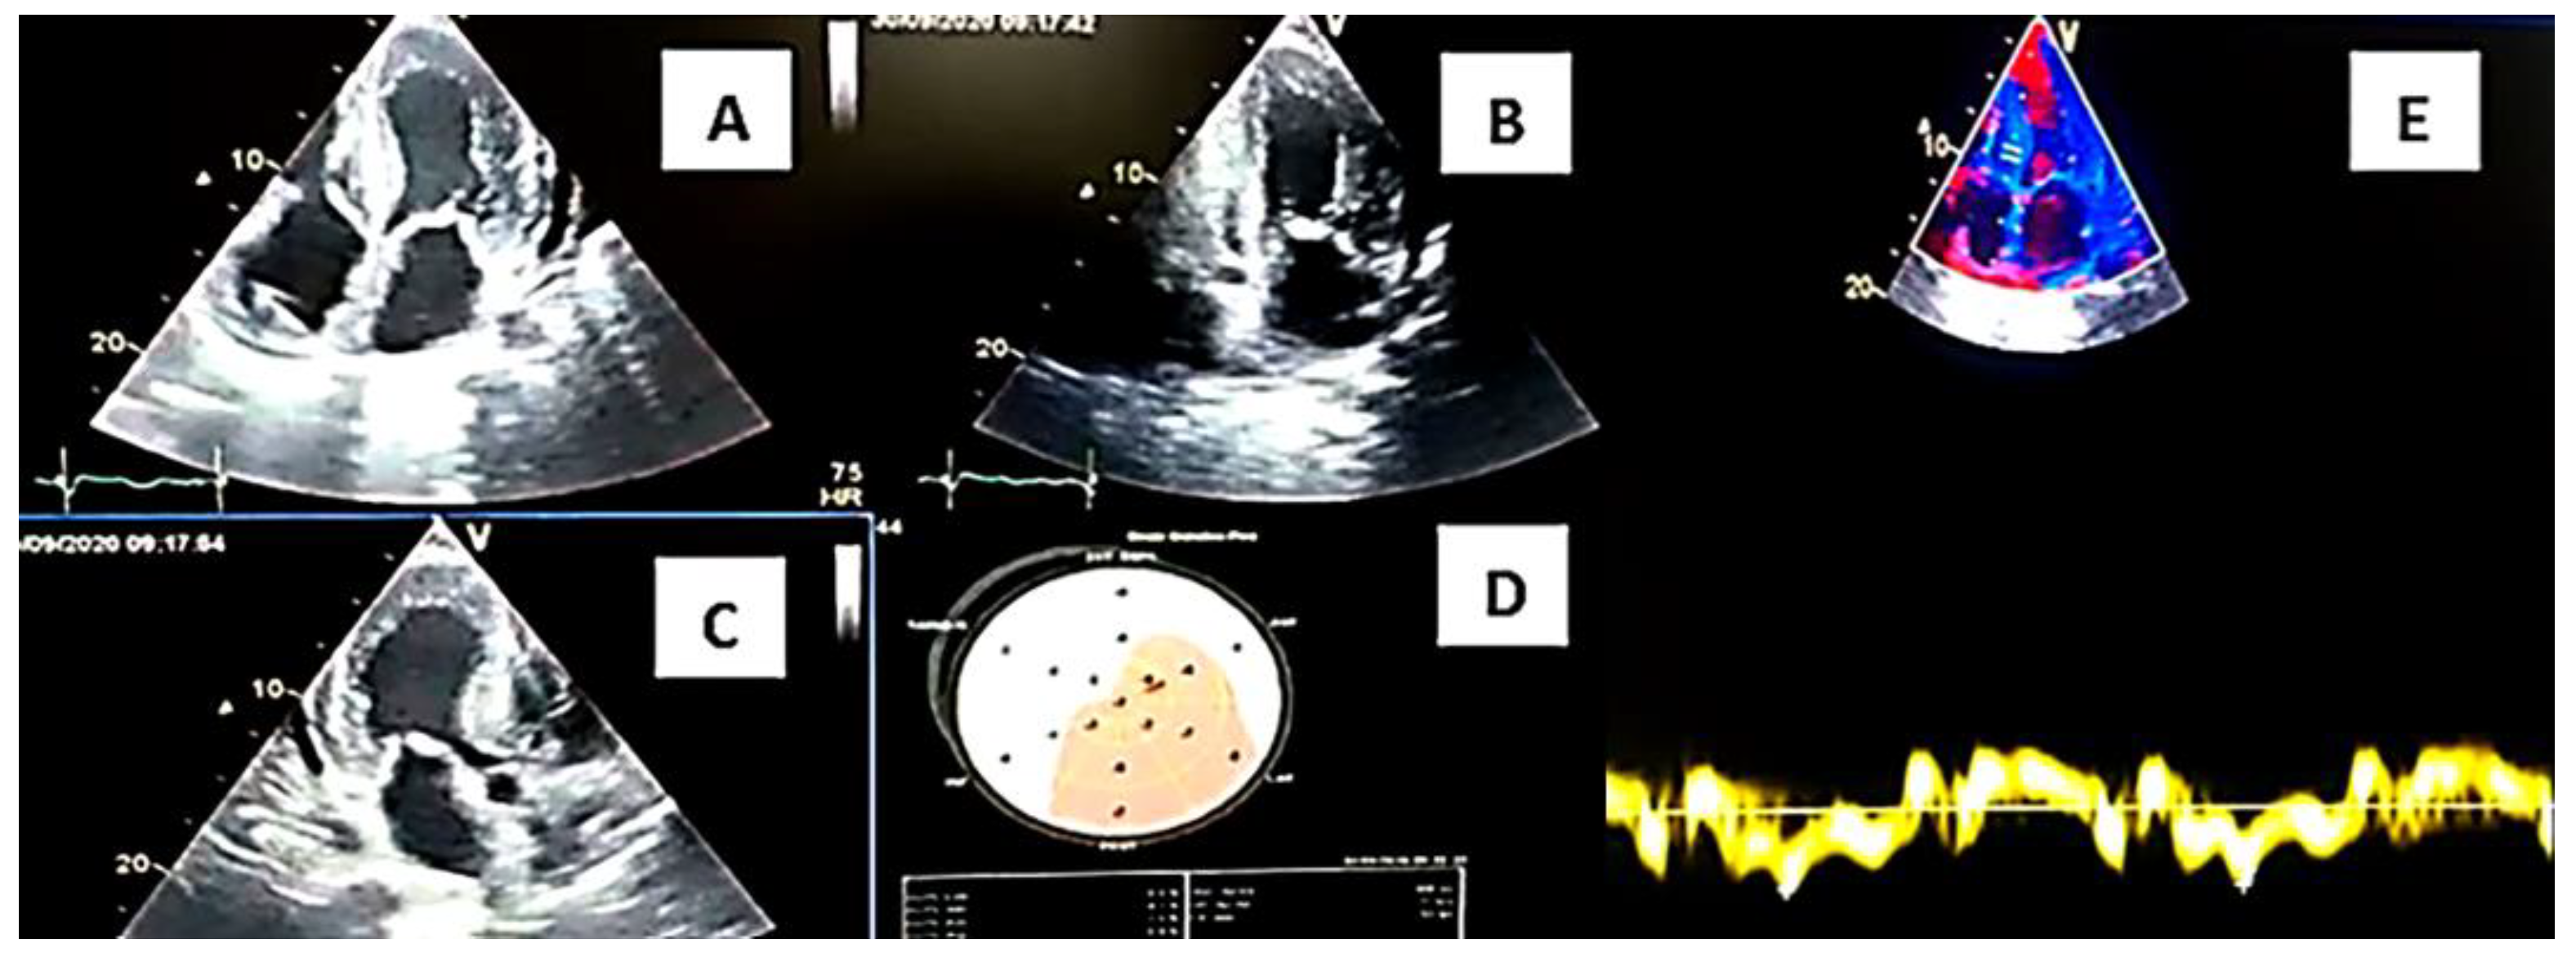

| Myocardiopathy on echocardiogram | Yes | Yes | Yes |